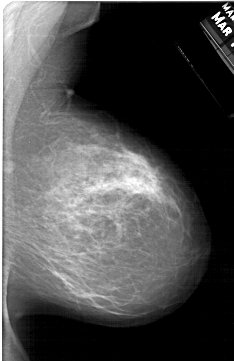

A_1217_1.LEFT_MLO

LEFT_MLO LINES 5881 PIXELS_PER_LINE 3751 BITS_PER_PIXEL 12 RESOLUTION 43.5 OVERLAY